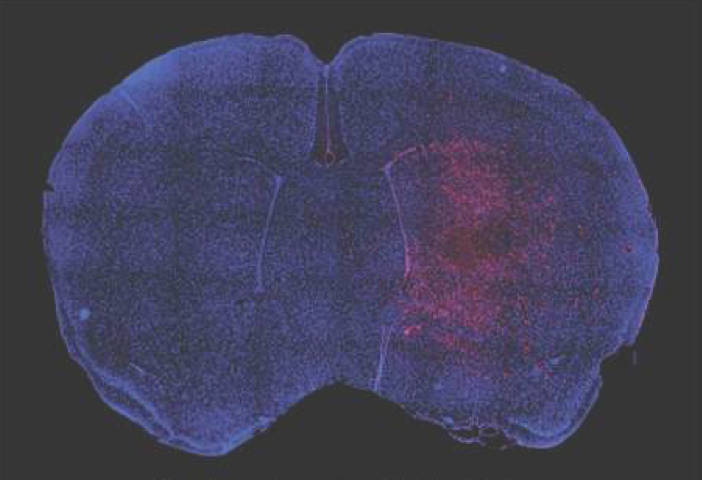

DECEMBER 5, 2017, New publication from the Aronin lab. Artificial miRNAs reduce human mutant Huntingtin throughout the striatum in a transgenic sheep model of Huntington's disease. Pfister E, Dinardo N, Mondo E, Borel F, Conroy F, Fraser C, Gernoux G, Han X, Hu D, Johnson E, Kennington L, Liu P, Reid S, Sapp E, Vodicka P, Kuchel T, Morton AJ, Howland D, Moser R, Sena-Esteves M, Gao G, Mueller C, DiFiglia M, Aronin N. Hum Gene Ther. 2017 Dec 5. doi: 10.1089/hum.2017.199.

AUGUST 23, 2017 RTI Gallery of images LIVE as a Cell Picture Show, hosted by the publisher of the journal Cell. To look at all of the images in this gallery, click here. For more information, see this link to our UMassMedNow article here.